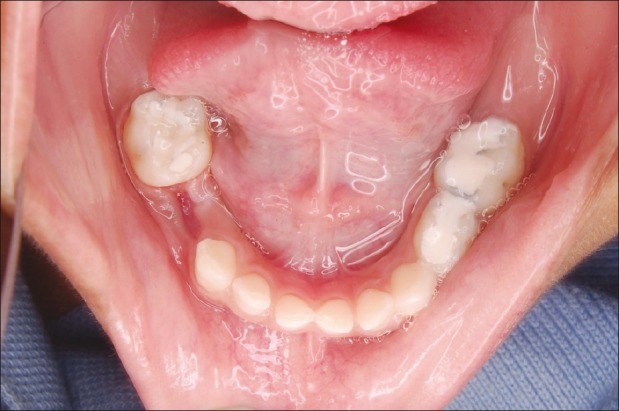

Đây là thời kỳ thích hợp nhất để hướng dẫn cắn khớp và ngăn chặn sai khớp cắn. Nha sĩ sẽ có thách thức lớn nhất cũng như cơ hội tốt nhất để tiến hành điều trị có hiệu quả. Lí do điều trị: a) Loại bỏ các cản trở sự phát triển bình thường của bộ răng. b) Điều trị sai khớp cắn ở bộ răng vĩnh viễn không thể hiệu quả hơn. Điều trị tập trung vào việc hướng dẫn tăng trưởng, ngăn ngừa sự phát triển của sai khớp cắn và lọai bỏ các dấu hiệu đầu tiên mà có thể làm cho sai khớp cắn trở nên trầm trọng hơn ở giai đoạn răng vĩnh viễn. Các trường hợp cần điều trị: a) Sự mất răng sữa gây nguy cơ thiếu khoảng trên cung hàm. b) Sự đóng khoảng do sự mất sớm các răng sữa. Khoảng bị mất trên cung hàm cần phải được hồi phục.

c) Răng mọc sai vị trí gây cản trở phát triển chức năng cắn khớp bình thường, gây rối loạn mọc răng hoặc há ngậm miệng, hoặc gây ảnh hưởng xấu đến sức khỏe răng miệng. d) Răng thừa có thể là nguyên nhân gây sai khớp cắn e) Khớp cắn chéo ở răng vĩnh viễn

g) Thiếu răng nếu đóng khoảng sớm có thể tránh làm răng giả h) Khe thưa giữa các răng cửa giữa hàm trên có điều trị chỉnh nha i) Khớp cắn bình thường nhưng có vẩu xương hàm trên quá mức j) Khớp cắn loại II type chức năng k) Khớp cắn loại II do răng

l) Khớp cắn loại II do xương, đặc biệt trong trường hợp điều trị hai pha được chỉ định m) Thiếu khoảng nhìn thấy rõ Các trường hợp có thể điều trị: các điều kiện có thể điều trị ở giai đoạn hàm răng hỗn hợp là: a) Sai khớp cắn loại II do xương, đặc biệt trong trường hợp điều trị hai pha được chỉ định b) Sai khớp cắn loại III mà điều trị sớm có khả thi c) Tất cả các sai khớp cắn mà răng quá to, nếu có chỉ định nhổ răng hướng dẫn thì cần điều trị sớm từ lúc giai đoạn răng hỗn hợp. d) Mất hài hòa nền xương 3. Kế hoạch điều trị ở hàm răng vĩnh viễn